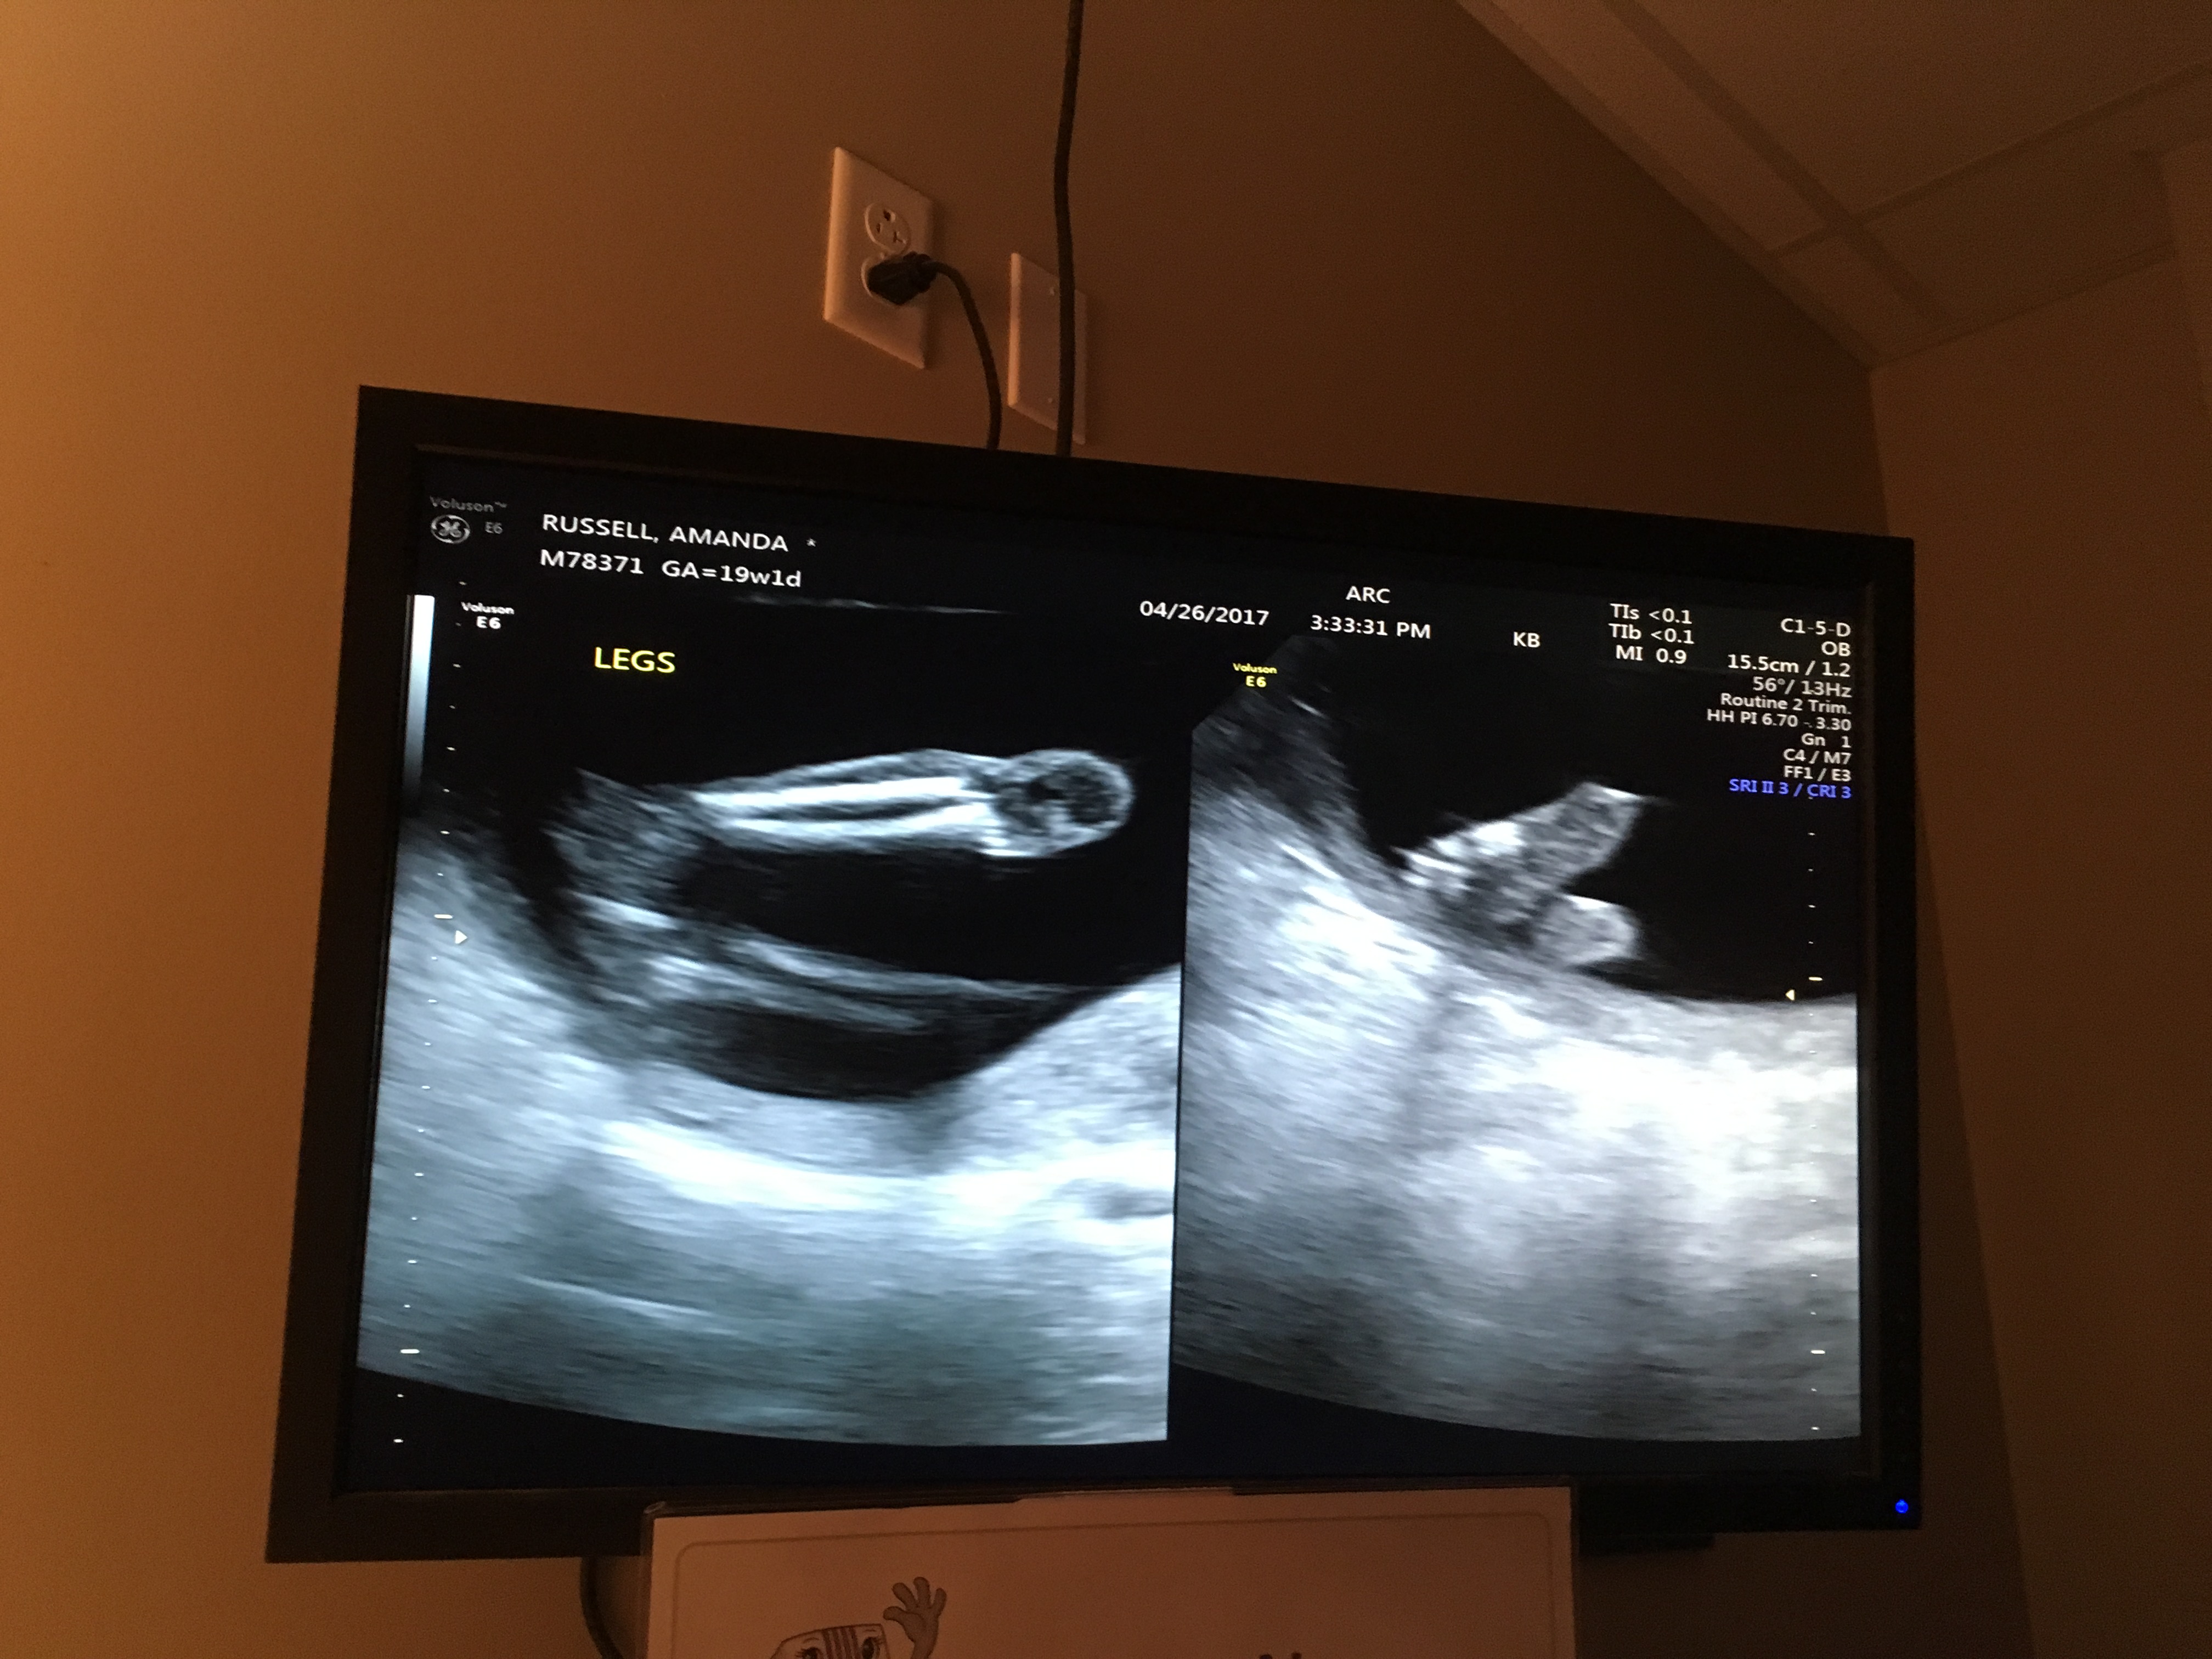

20 weeks and team green! Guesses please??

Was told maybe boy at 12 weeks but since then we decided to wait! Still would love guesses for fun....I'm not banking on anything don't worry ;)

Attachment 36047